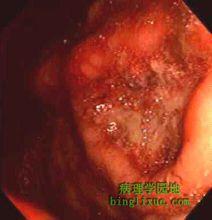

澱粉樣變病2.內鏡檢查內鏡下胃黏膜色澤發黃,常伴有散在性白斑,黏膜皺襞可表現紅、腫、肥大。但這些表現均缺乏特異性。結腸鏡下常觀察到與潰瘍性結腸炎類似的表現,即黏膜水腫、糜爛、瀰漫性黏膜發紅及潰瘍。有的還可以出現息肉樣改變。下消化道出現梗阻症狀時,在乙狀結腸有時可以看到與BorrmannⅢ型癌難以鑑別的隆起性潰瘍。3.活組織檢查本病惟一的診斷方法是在活檢組織中確認澱粉樣纖維沉積。過去全身性澱粉樣變病的活檢部位為齒齦、舌、小腸、直腸,其中直腸活檢最為普通。近年很多報告提出胃活檢比直腸活檢簡單而且診斷率也高。必要時可對胃、直腸都進行活檢。活檢時應注意取足夠的深度,為此內鏡插入時應少注氣,選擇視野良好的部位,使用較大的活檢鉗,鉗子接觸到黏膜後,應稍加壓力,以便儘可能取材深些。胃活檢應該取到黏膜肌層。一般從胃角到胃竇需要取5~6塊組織。直腸活檢有必要取到黏膜下組織,一般在距肛門10~15cm處後壁取5~6塊組織。活檢後應注意止血。活檢組織經剛果紅染色在偏光顯微鏡下觀察澱粉樣蛋白特有的綠色雙折射可確診。根據活檢標本上的澱粉樣纖維沉積型來判定澱粉樣變病的分型是困難的。特異的組織觀察要求通過電鏡確認澱粉樣纖維,並套用各種染色綜合判定澱粉樣蛋白的免疫組織類型。